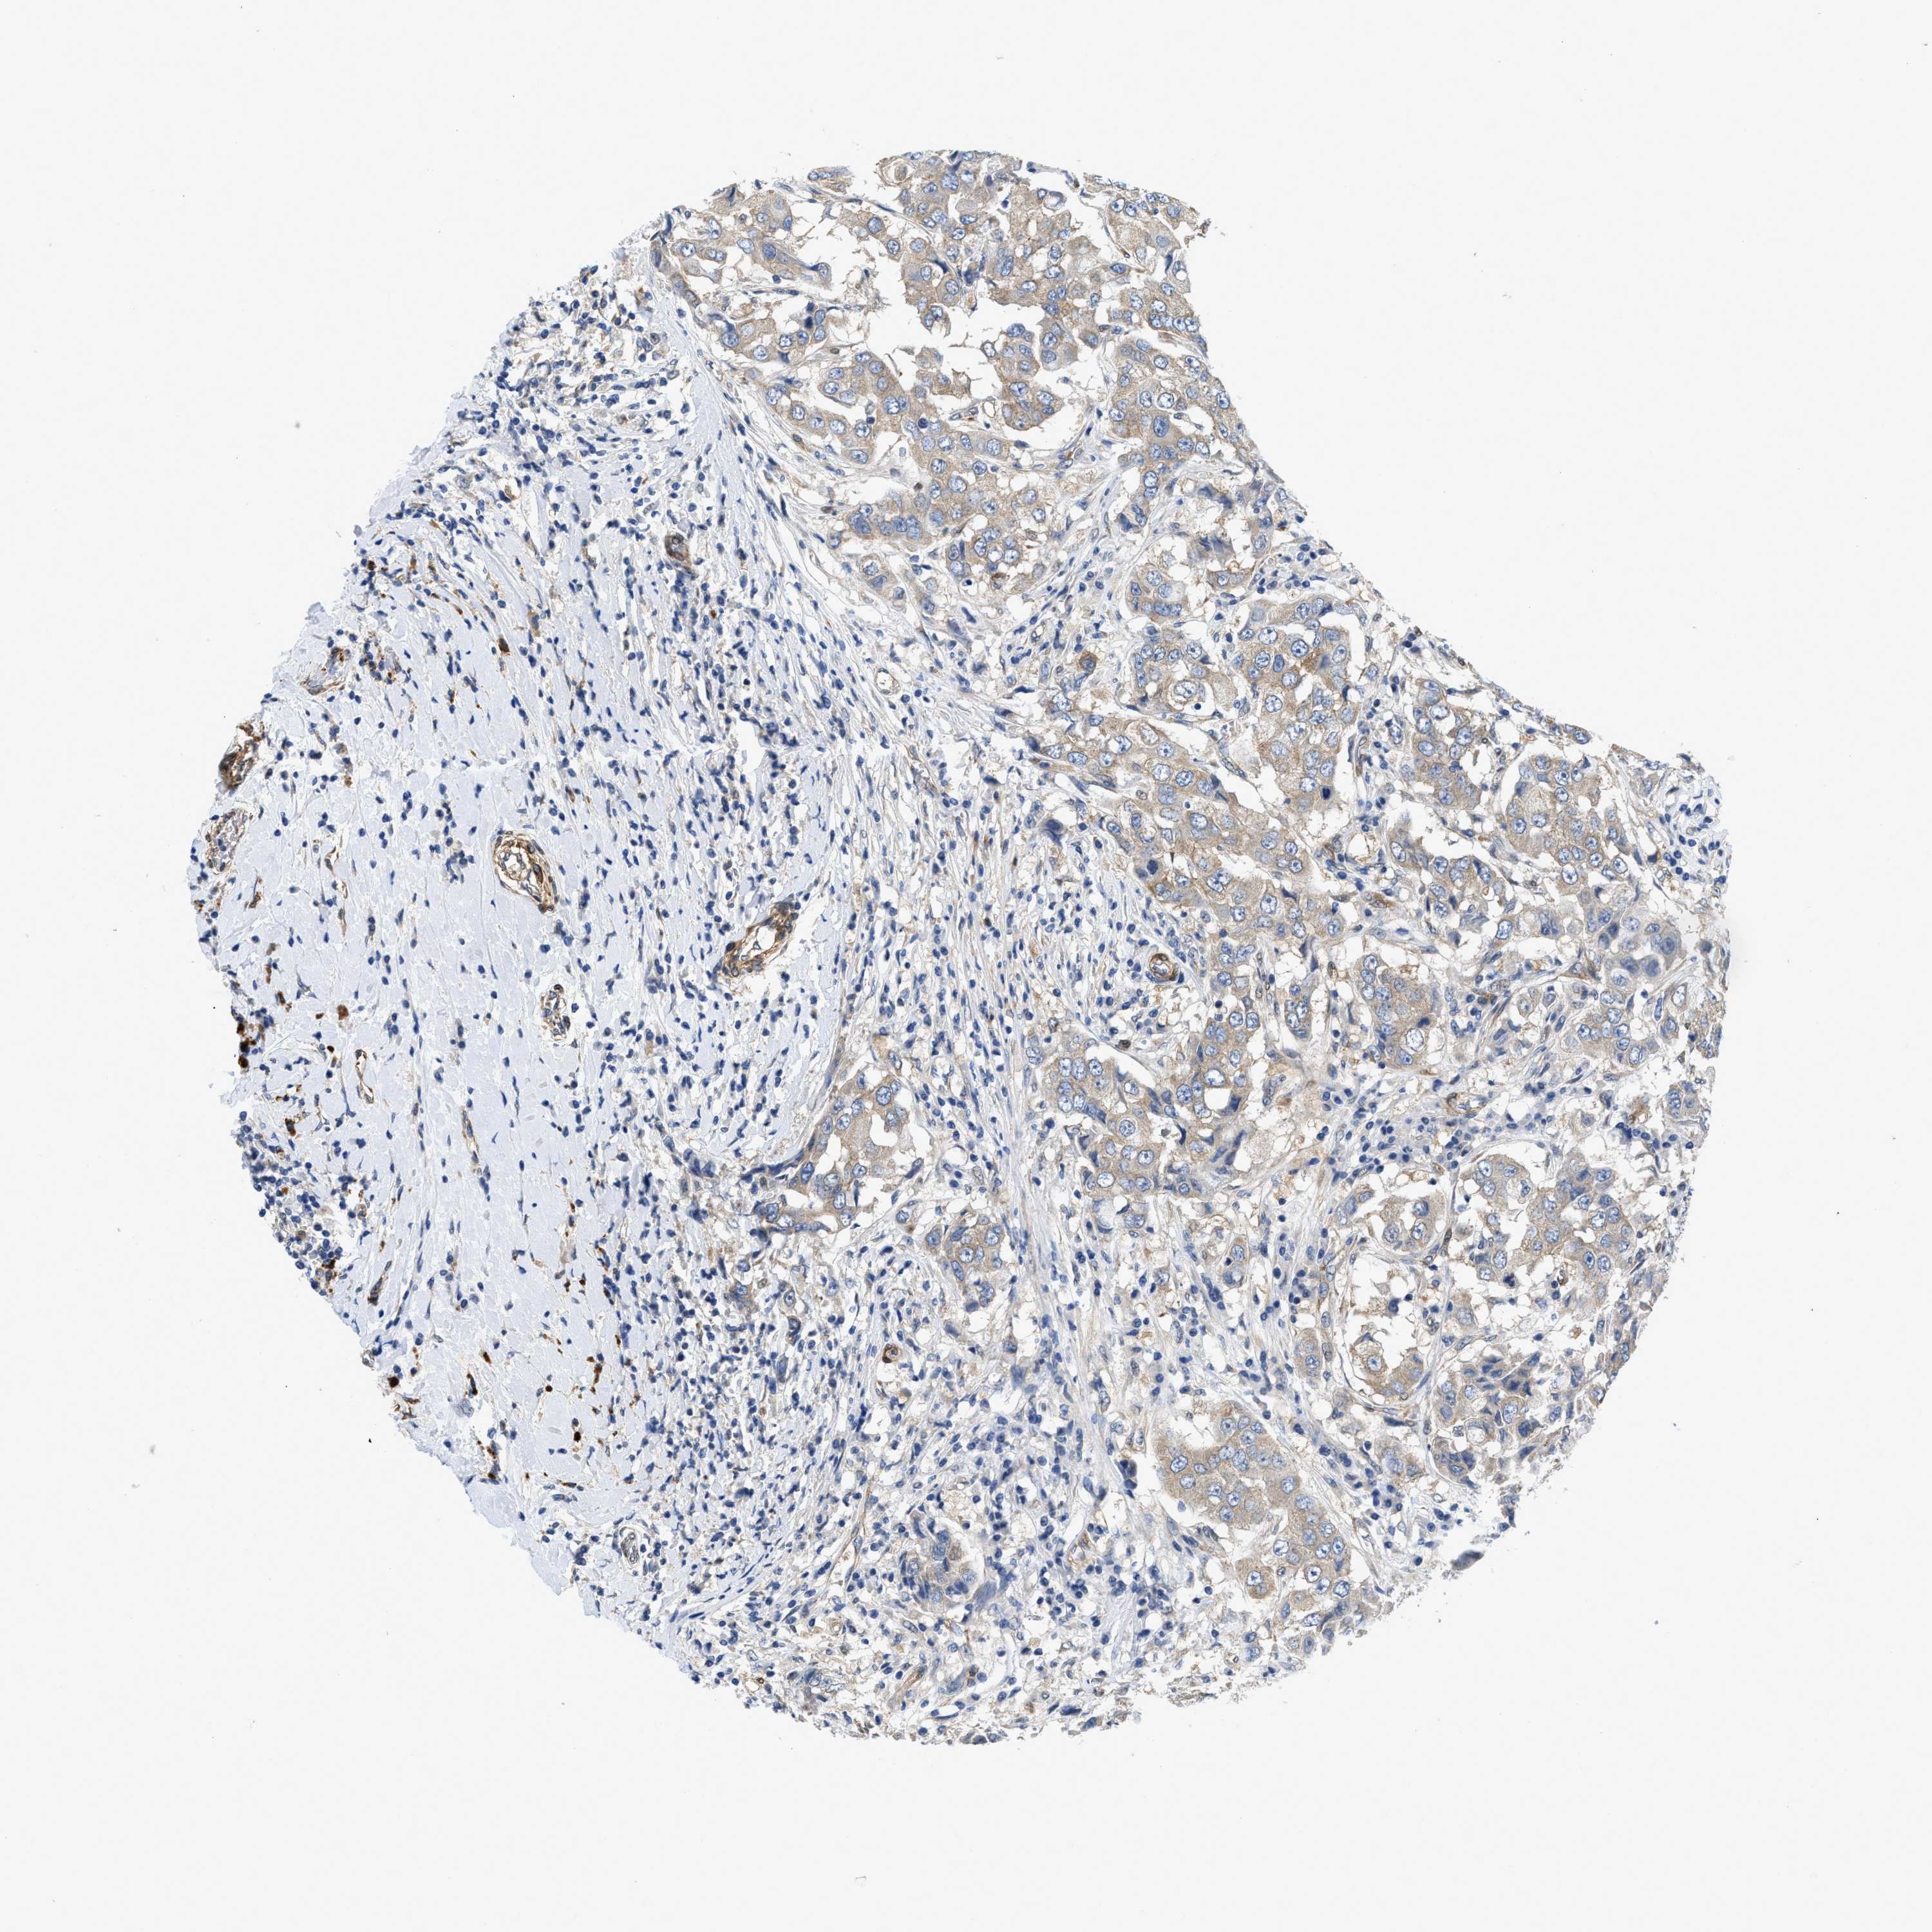

CANCER BREAST CANCER Show tissue menu

BRCA TCGA BRCA VALIDATION PROTEIN EXPRESSION

RAPH1 is not prognostic in Breast Invasive Carcinoma (TCGA)